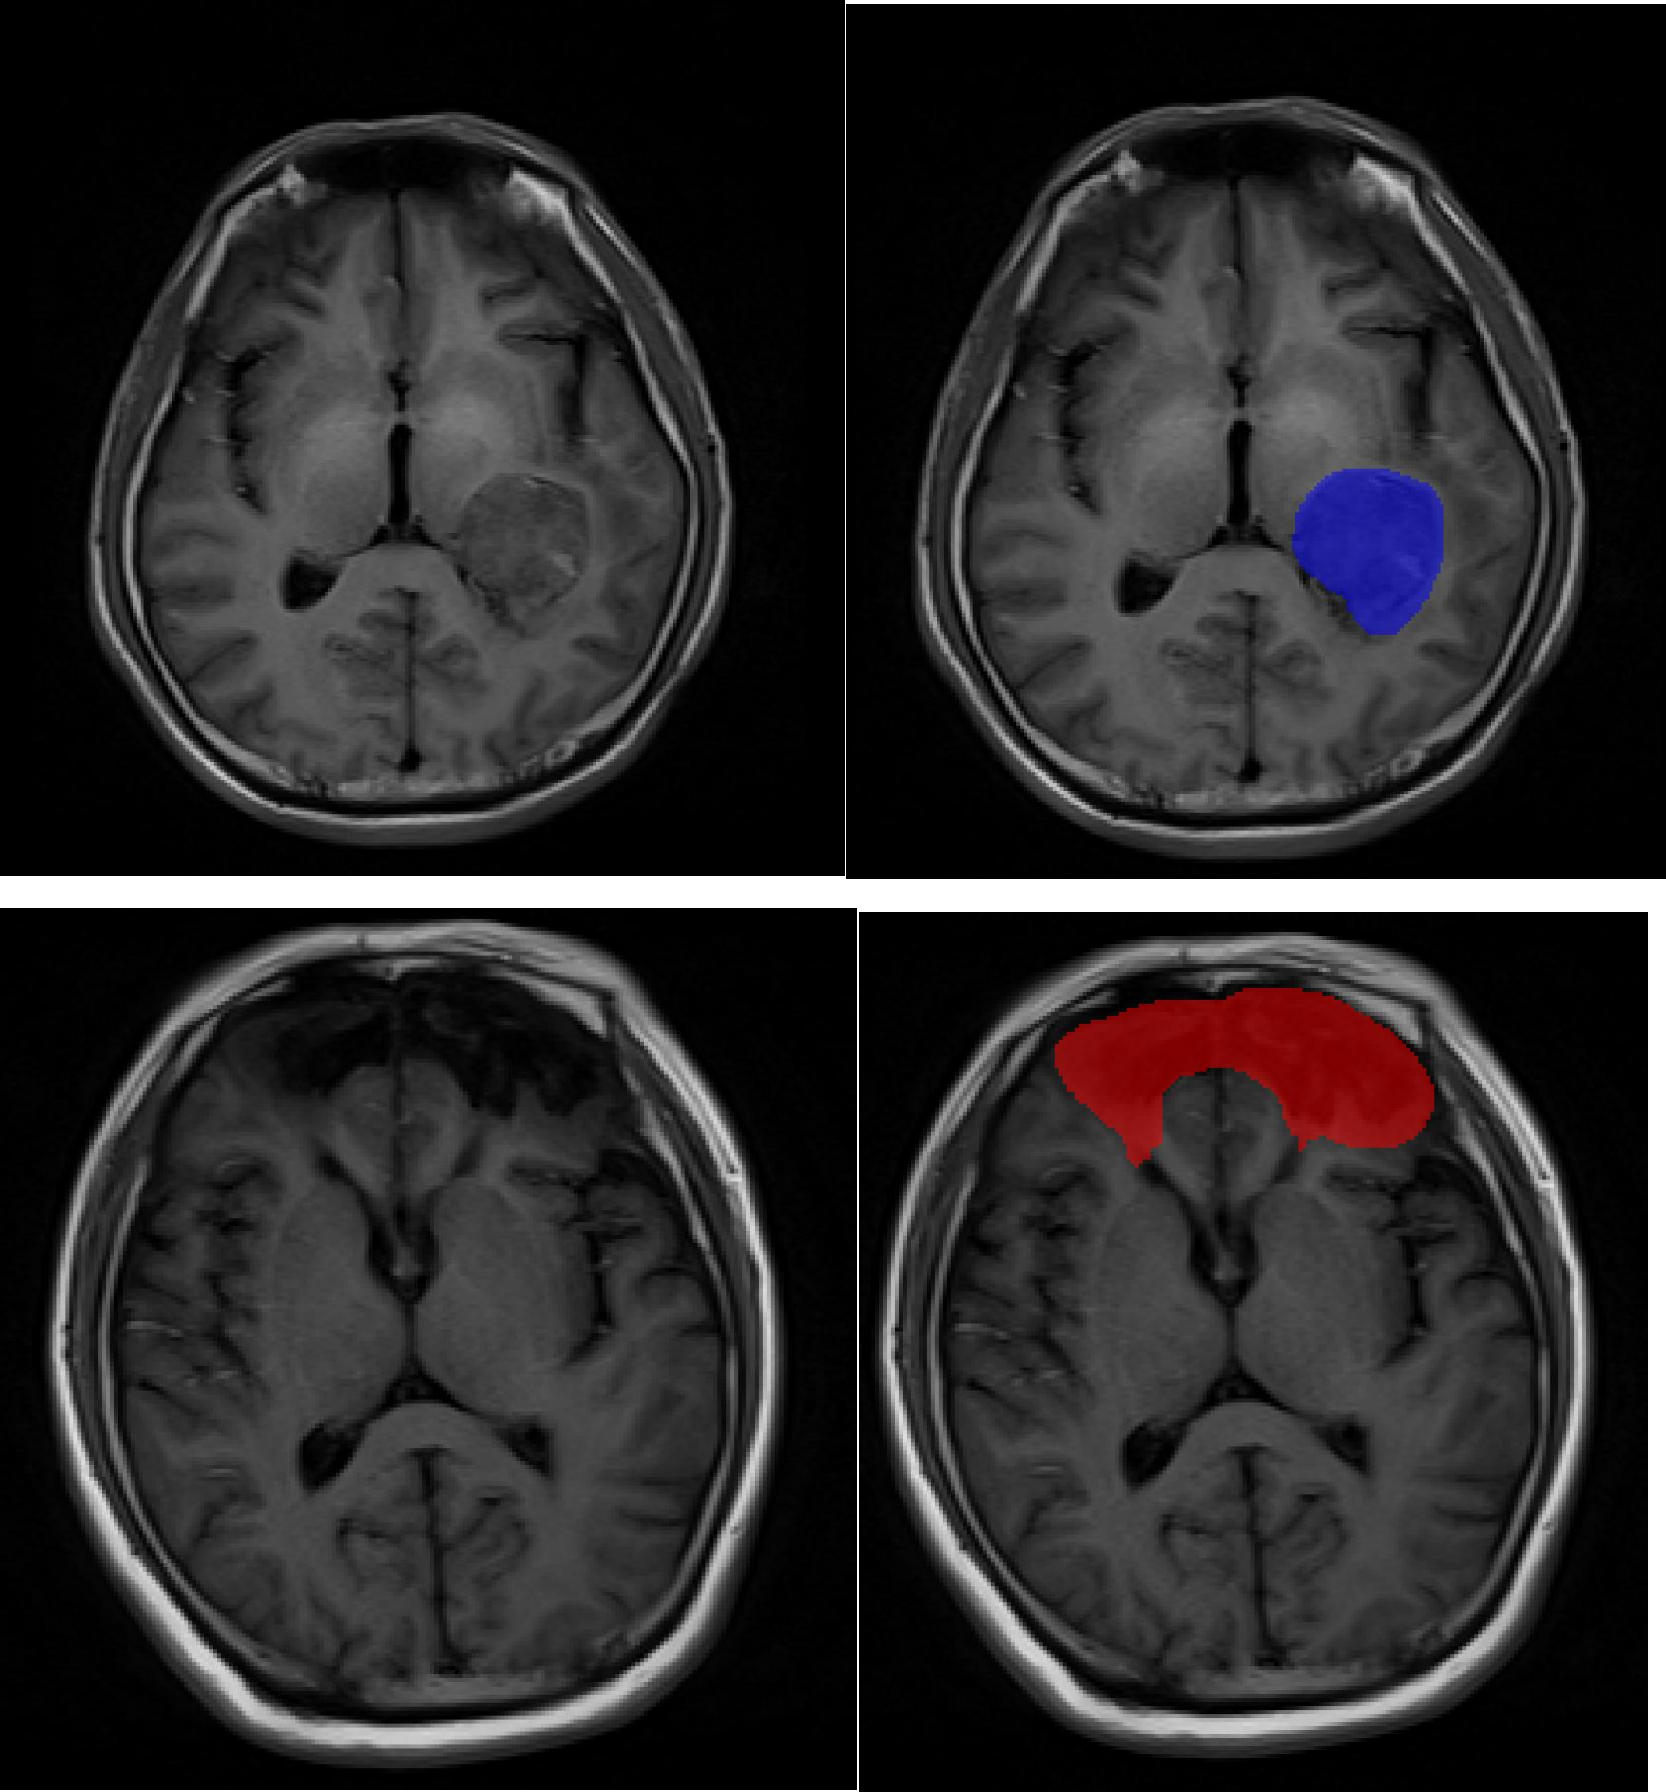

长沙朗慧信息科技有限公司是一家专注于数据标注服务的创新型企业,秉持 “数据驱动,智能创新” 理念,依托人工智能技术和大数据分析,提供高质量、准确、高效的数据标注解决方案。其服务聚焦医疗数据领域,涵盖医学影像、医疗文本及多模态数据融合标注等,通过智能辅助标注、多轮交叉校验等方式保障质量与效率,旨在以数据标注为切入点,助力释放医疗数据价值,推动医疗健康行业智能化发展,用科技改变医疗数据的未来。